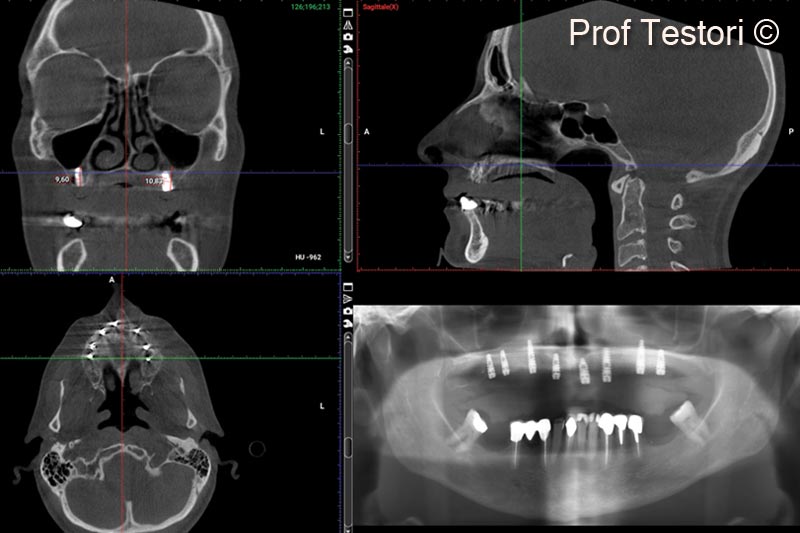

1. Pre-operative panorex and CBCT